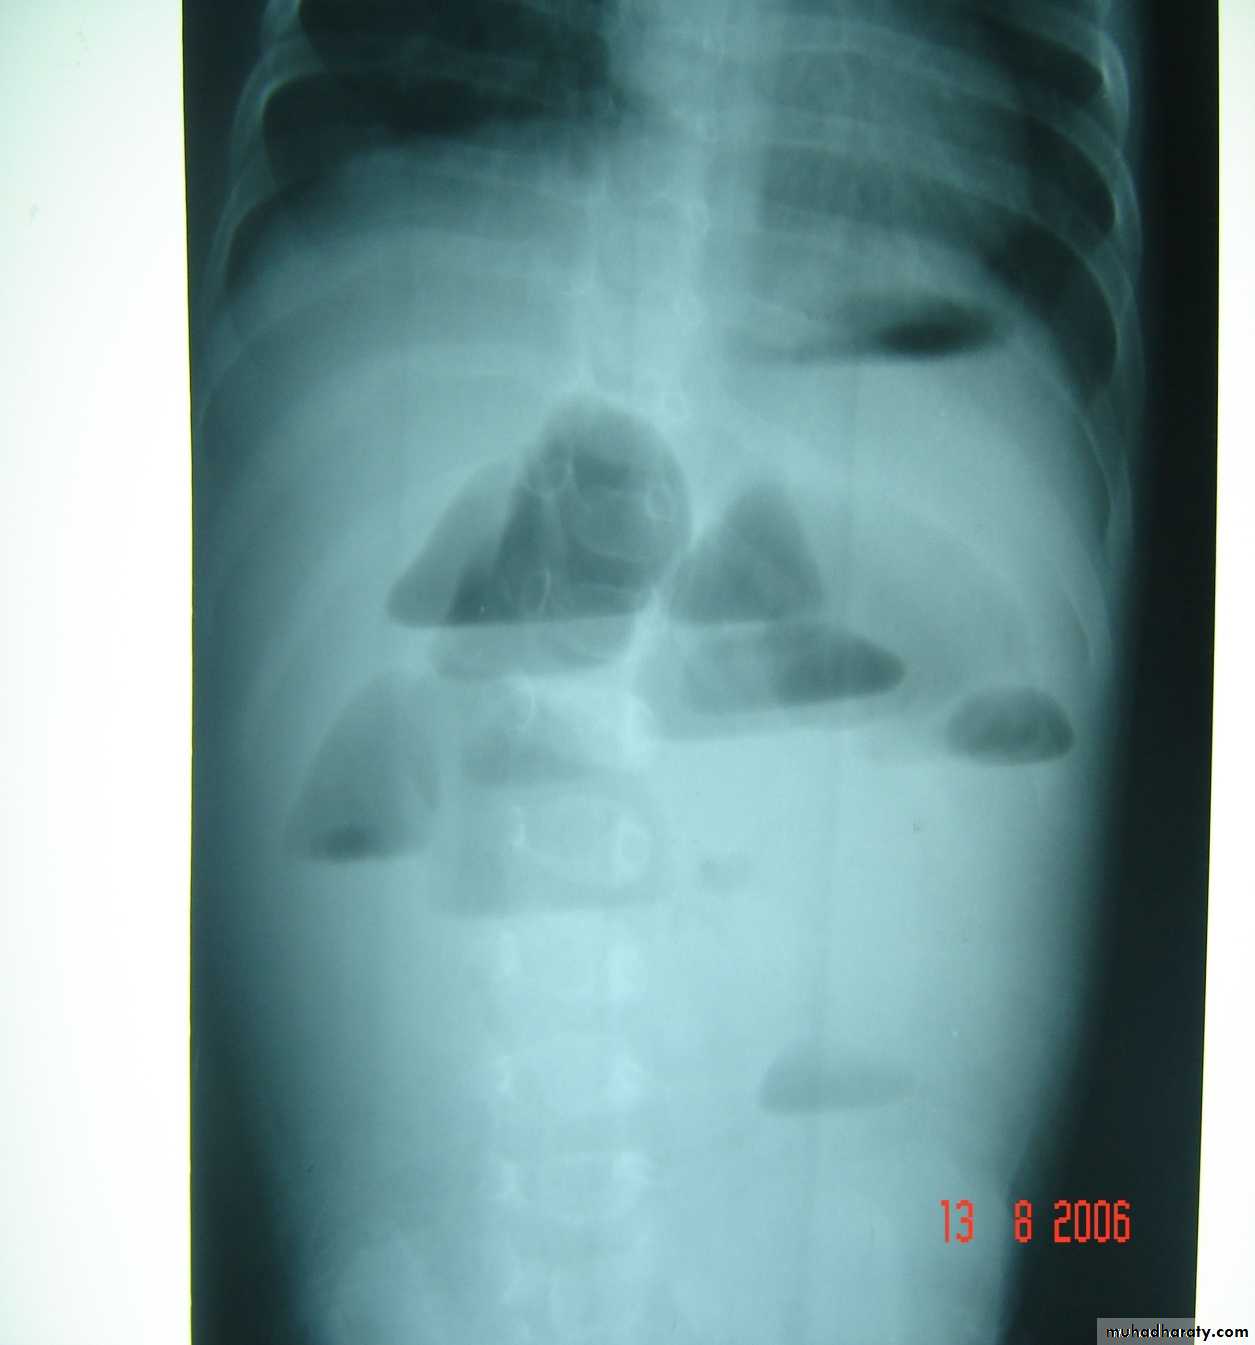

Meconium ileus+atresia